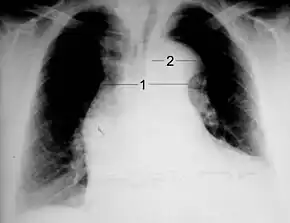

Chest X-ray

Chest radiography may demonstrate a change in shape of the thoracic aorta. Classically, new widening of the mediastinum is of moderate sensitivity for detecting an ascending aortic dissection; however, this finding is of low specificity, as many other conditions can cause apparent widening of the mediastinum.

There are several other associated radiographic findings:

- The "calcium sign" describes an apparent separation of the intimal calcification from the outer aortic margin by greater than 10 mm.

- Pleural effusions, more commonly in descending aortic dissections, and typically left sided.

- Other: obliteration of the aortic knob, depression of the left mainstem bronchus, loss of the paratracheal stripe, and tracheal deviation.

Importantly, about 12 to 20% of aortic dissections are not detectable by chest radiograph; therefore, a "normal" chest radiograph does not rule out the condition. If there is high suspicion, a more sensitive imaging test (CT angiogram, MR angiography, or transesophageal echo) may be warranted.

1 Aorta descendens with dissection

2 Aorta isthmus